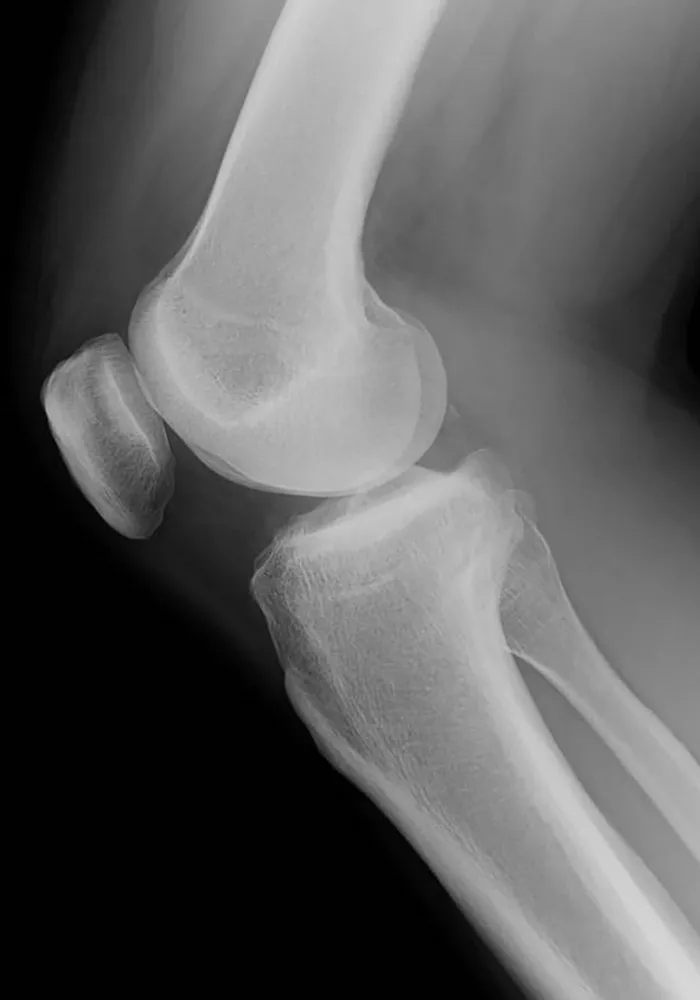

MRI(核磁気共鳴画像診断装置)

MRIは Magnetic Resonance Imaging(磁気共鳴画像) の略で、放射線を使用せず、強力な磁石と電磁波を使って体の断面画像を撮影する装置です。MRI検査では様々な病巣を発見することができますが、特に脳や、脊椎、四肢、腹腔内臓器(肝・胆・膵)また子宮、卵巣、前立腺等の骨盤腔に生じた病変に関して優れた描出能が知られています。また、色々な病気の早期発見、診断にMRI検査は有効とされています。また、血管を抽出するMRA(MR-Angiography)や胆管・膵管を抽出するMRCP(MR-Cholangio Pancreatography)といった撮像も可能です。検査内容によってMRI用造影剤を使用する場合があります。造影剤使用の有無は必要に応じて医師が判断いたします。